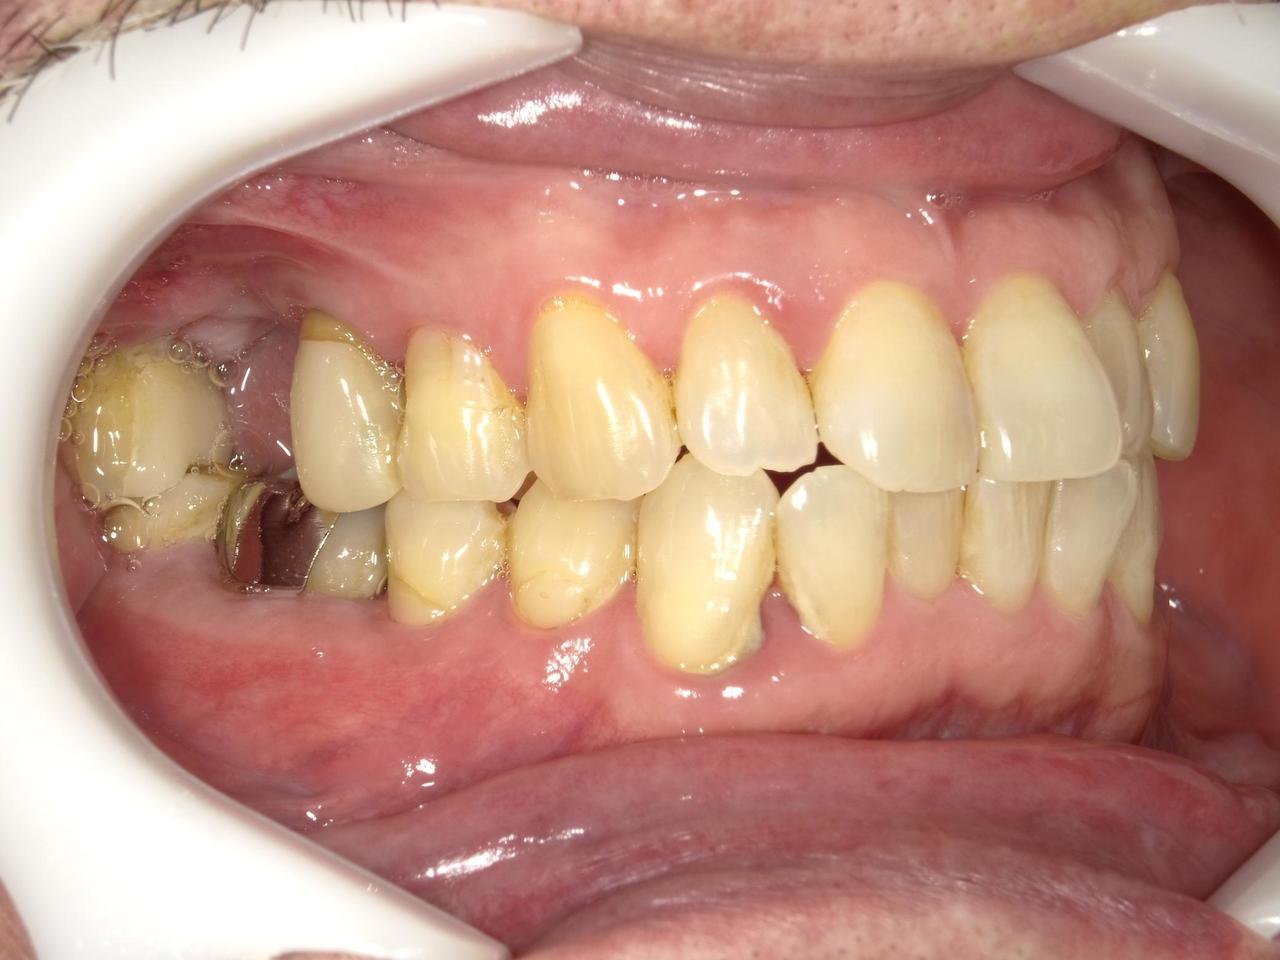

Before

枚方市のインプラントの症例

M・I 様 女性 70代

症状としては、左下56は、歯周病で欠損したと考えられるが、かなりの骨欠損をともなっていた。左上456に関しては、動揺が大きく、炎症が起き、排膿、および、歯性上顎洞炎を起こしていた。

治療法としては、動揺がひどくなってきて、炎症の症状もあったため、左上56の抜歯を希望。インプラント治療をその後、希望したため、左上4に関しては抜歯即時埋入。左上6に関しては、既存骨1から2mmでインプラント治療が厳しい状態であったが、グラフトレスサイナスリフトを行い、治療期間5か月はかかるということを説明して、インプラント埋入をおこないました。その後、2か月半後、大幅に骨が欠損している下顎56に対して、ショートインプラントを使用して、下顎神経の損傷を避けて、インプラント埋入を終えています。その後2か月後に光学印象で印象を行い、上顎刺億456歯、3ユニットのジルコニアブリッジを装着。下顎左側56に関しては、骨欠損が大きいため、歯冠長がだいぶ長くなるため、ジルコニアの連結冠を装着して治療を終えた。

治療結果は、上顎6に関しては、既存骨が少なく、厳しい治療ではありましたが、5か月で治療を終え、患者様の負担を最小限に抑えるができたと考えます。(従来のサイナスリフトでは、このようなケースでは1年以上、1年程度の治療期間がかかるか、治療が不可能と言われるケースだと考えます。)また、下顎は骨欠損が大きく、下歯槽管のリスクが起きることが考えられますが、ショートインプラントを使用することで安全に治療を行うことができました。

治療の期間・回数:治療期間5か月(上顎456 3ピースブリッジの治療は5か月(上顎既存骨が2mm程度しかなく、骨結合に時間がかかるケースであったために、5か月の治療期間が必要であった。)(左下56に関しては2か月半で治療を終えています。)治療回数は、13回。

治療の価格:1,474,000円(税込)

治療費の内訳:左上46および左下56のインプラント基本料(フィックスチャー及び手術費用、投薬費用、レントゲン費用、インプラント上部費用(アバットメントおよびジルコニアクラウンの費用用)330000円(税込み)×4本分 1320000円(税込)。左上5ジルコニアポンテック費用88000円(税込)。オプション費用、左上4抜歯即時埋入加算(人工骨費用を含む)+グラフトレスサイナスリフト費用 33000円(税込)、左上6グラフトレスサイナスリフト費用 33000円(税込)

治療のリスクや副作用:手術後に、痛みや腫れ、出血、合併症などを引き起こす可能性があります。噛む感覚がご自身の歯と異なる場合があります。見た目がご自身の歯と異なる場合があります。手術後にメインテナンスを継続しないと、インプラントが抜け落ちる可能性があります。